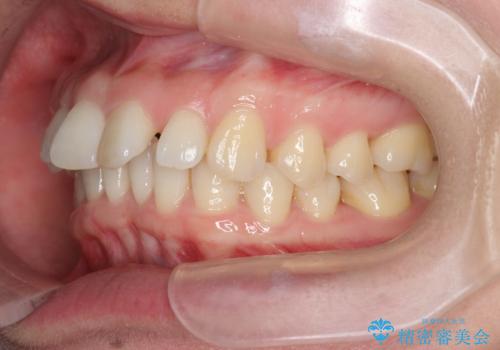

インビザライン で治す 出っ歯の治療

- 前歯の突出感、出っ歯の治療を希望され来院されました。

インビザラインを用いた治療計画を立て、しっかりと出っ歯を治すためにマイクロインプラントを併用します。

マイクロインプラントを併用することでしっかりとマウスピース全体を後方へ引き、前歯の突出感を改善することができました。